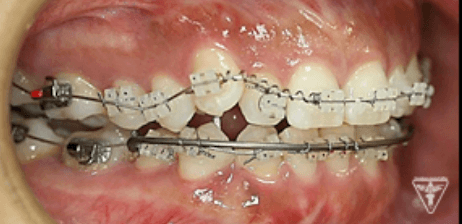

治療過程②